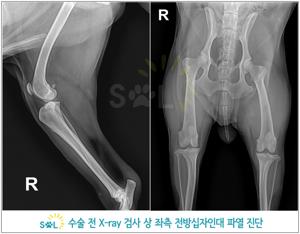

진단 방법

- 임상 증상과 이학적 검사(무릎의 불안정성 확인)

- 방사선(X-ray) 촬영

소형견에서는 십자인대 파열이 대형견에 비해 상대적으로 드물게 발생하지만, - 최근에는 비만한 소형견에서 그 빈도가 증가하는 추세입니다.

- 또한, 소형견은 선천적으로 연골이 약해 슬개골 탈구가 흔한데,

- 이 슬개골 탈구가 장기적으로 십자인대 파열로 이어질 수 있습니다.

- 즉, 소형견에서는 슬개골 탈구가 십자인대 파열의 위험인자로 작용하는 경우가 많습니다.

소형견은 고령(10세 전후)에 십자인대 파열이 생기는 경향이 있습니다. - 슬개골 탈구를 오래 방치한 경우, 나이가 들면서 인대가 약해져 파열로 이어질 수 있습니다.